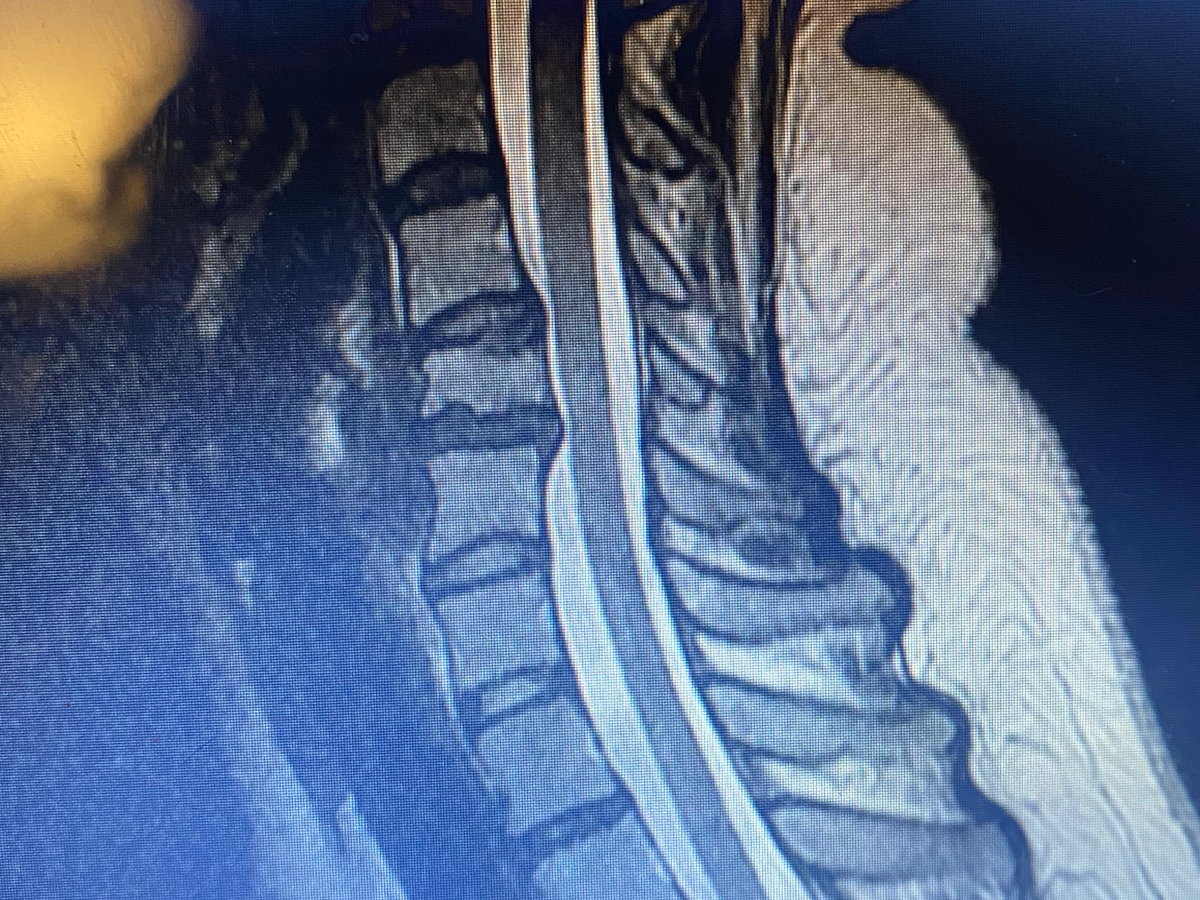

Hey all, my name is Felicia Tomolonis. This is really embarrassing, but on July 5th 2025 I was diagnosed with a concussion, which unfortunately has made my anxiety/depression/ptsd worse. It has also worsened the condition of my neck, causing more neck and nerve pain than ever before. Due to this, I’m currently out of work on short term disability. I hope to return asap and as soon as medically cleared, but with everything going on I don’t really know what else to do.

On imaging, an abdominal hernia was found that will need to be surgically repaired. It’s currently causing pain when I breathe, so working right now just seems impossible. I want to work and go back asap, because I truly can’t afford to not have help with only 60% of my earnings.